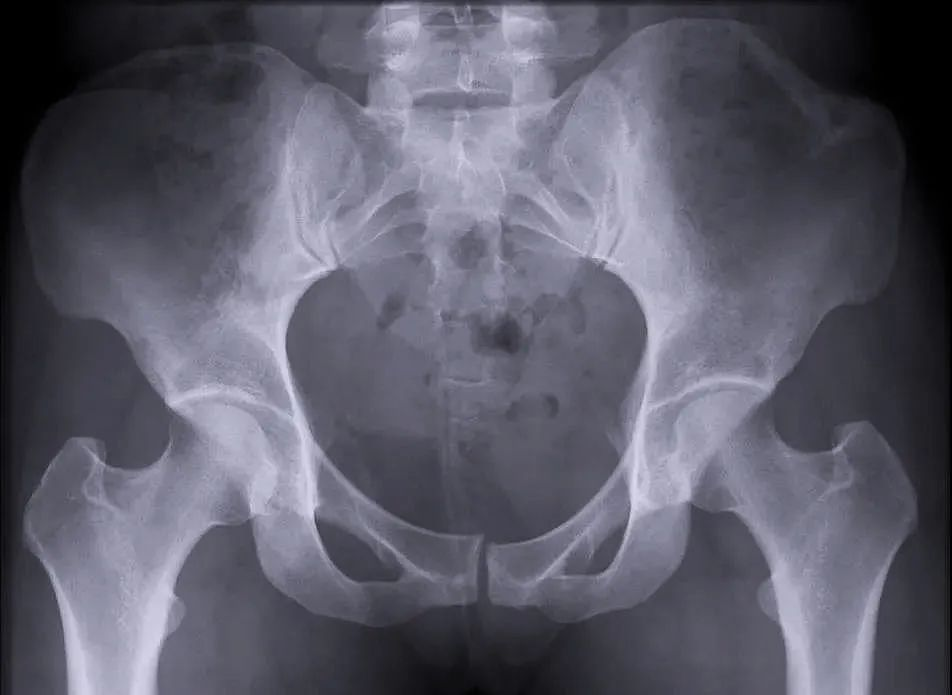

【醫療科普】:病理性骨折影像

病理性骨折:多發性骨纖維異常增殖癥